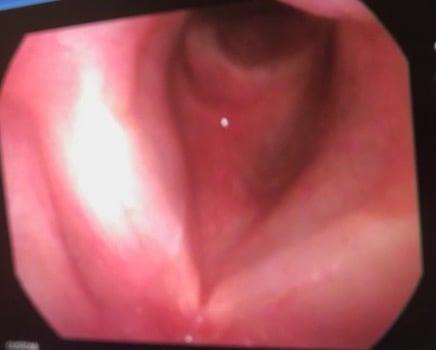

Laryngology

Endoscopic techniques

Microlaryngeal surgery